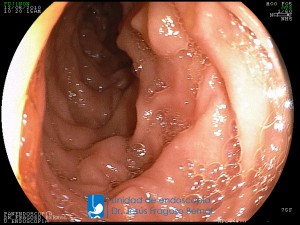

La Unidad de Endoscopía fue creada en 2002 por el Dr. Jesús Fragoso Bernal, es pionera en el estado por la utilización de la tecnología más avanzada, que nos permite ofrecer servicios integrales de diagnóstico y tratamiento para las enfermedades del aparato digestivo.